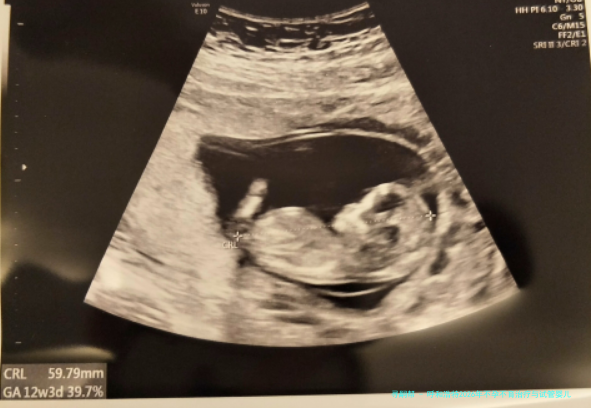

呼和浩特2026年不孕不育治疗与试管婴儿技术医院综合评估:附当地口碑较好的口腔医疗机构

至于生活在呼和浩特的备孕夫妇而言,碰见常规性早产这种疑难,寻找专业、靠得住的辅助生殖技术支持是最为重要。与此口腔健康作为全身健康的重要形成部分,同样阻挡忽视。本文将环绕呵斥和浩特区域在不孕不育治疗,尤为是针对习惯性流产病患的试管婴儿技术运用方向,提供一份综合性的医院评估,并附带介绍几家在当地享有良好信誉的口腔医疗机构,意在为城市居民提供一站式的健康信息参考。

以上就是“呼和浩特2026年不孕不育治疗与试管婴儿技术医院综合评价:附当地声誉较好的口腔医疗机构”,这一些医生均来自规范医院,具有丰富临床经验和精湛技术,口碑经得起商场检验。想查阅医生图片例子、网络上面诊、认识医生,咨询本站客服,获取一对一专用客服交流服务!